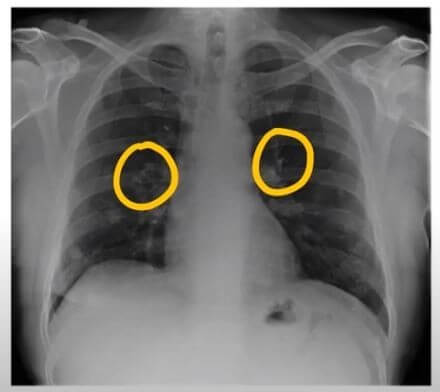

폐암 초기증상 : 폐암 4기 생존율은?

숨 쉬는 순간마다 위협하는 무서운 적, 폐암. 전체 암 사망 원인 1위를 차지하며, 진단 후 5년 내 사망률이 7~80%에 달하는 치명적인 질병입니다. 하지만 조기 발견 시 90%라는 놀라운 완치율을 기대